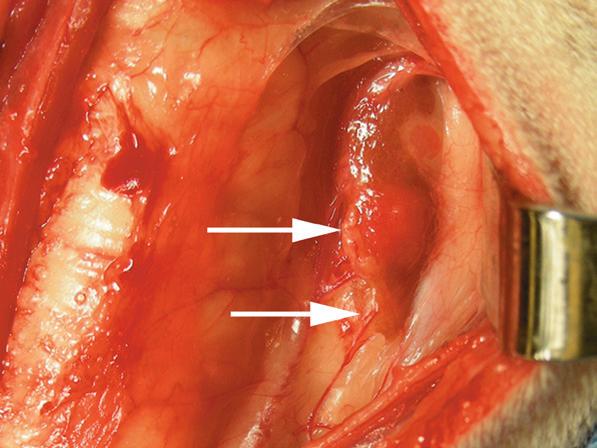

Rycina 1.11.6. Rak tarczycy i gruczolak tarczycy (pies) TK

Badanie wykonano u 12-letniej, kastrowanej samicy owczarka australijskiego z prawostronną masą w dobrzusznej części szyi. Badanie USG wykazało dużą, litą, unaczynioną masę w obrębie prawego płata tarczycy (a) oraz mniejszą, hipoechogeniczną masę w obrębie lewego płata (b). Obrazy TK przed i po podaniu środka kontrastowego (c–f) ułożone od doczaszkowych do doogonowych ukazują dużą, prawostronną, jednorodnie wzmacniającą się masę (c–f – duża strzałka) z niewyraźną granicą dobrzuszną oraz pozatorebkowym szerzeniem się i rozlanym wzmocnieniem pokontrastowym przyległych tkanek (e, f – grot strzałki). W obrazie bardziej doczaszkowym widoczny jest prawidłowy lewy płat (c, e – mała strzałka), natomiast w obrazie bardziej doogonowym jest on powiększony i ma niższą gęstość, niż można by oczekiwać, co sugeruje obecność drugiej, mniejszej masy (d, f – mała strzałka). W obrazach reformowanych wzdłuż osi długiej widać dwa małe guzki w lewym płacie (h – małe strzałki). Wyniki obrazowe potwierdzono podczas zabiegu (i, j – strzałki). Biopsja wycinkowa wykazała prawostronnego raka tarczycy z naciekaniem pozatorebkowym oraz lewostronnego gruczolaka tarczycy